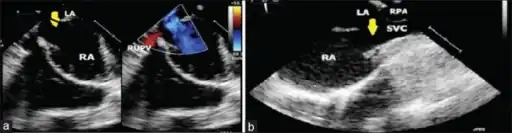

Image shows sinus venosus atrial septal defect and partial anomalous pulmonary venous connection